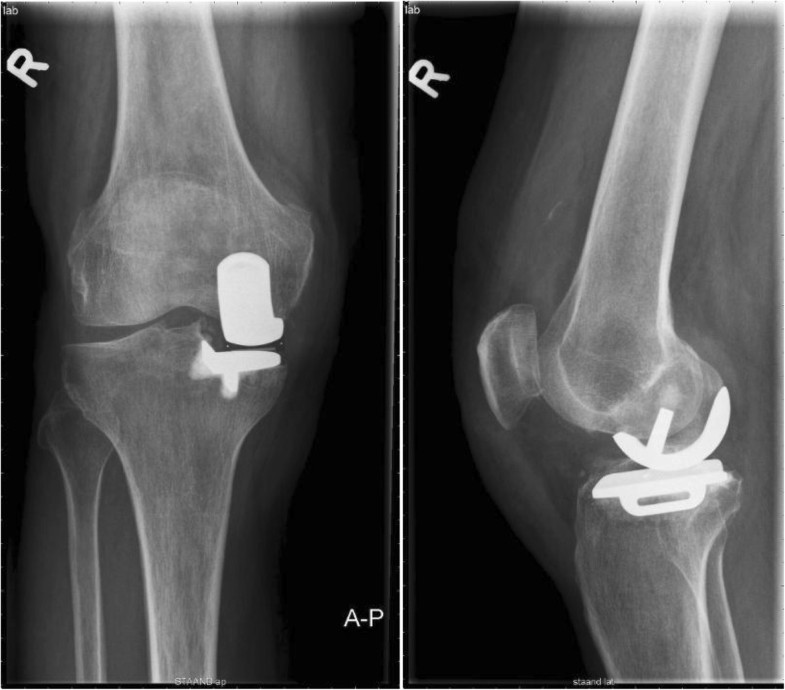

Figure 2 from Cementless Oxford knee replacement shows Oxford Criteria For Unicompartmental Knee Replacement Unicompartmental knee arthroplasty is a surgical option for knee arthritis when only one compartment of the knee is involved. Unicompartmental knee replacement (ukr) is a common treatment option for patients with advanced medial compartment knee arthritis. Oxford unicompartmental knee arthroplasty (uka) has been particularly prevalent because the concept of knee preservation is. The procedure can be performed for isolated medial.. Oxford Criteria For Unicompartmental Knee Replacement.